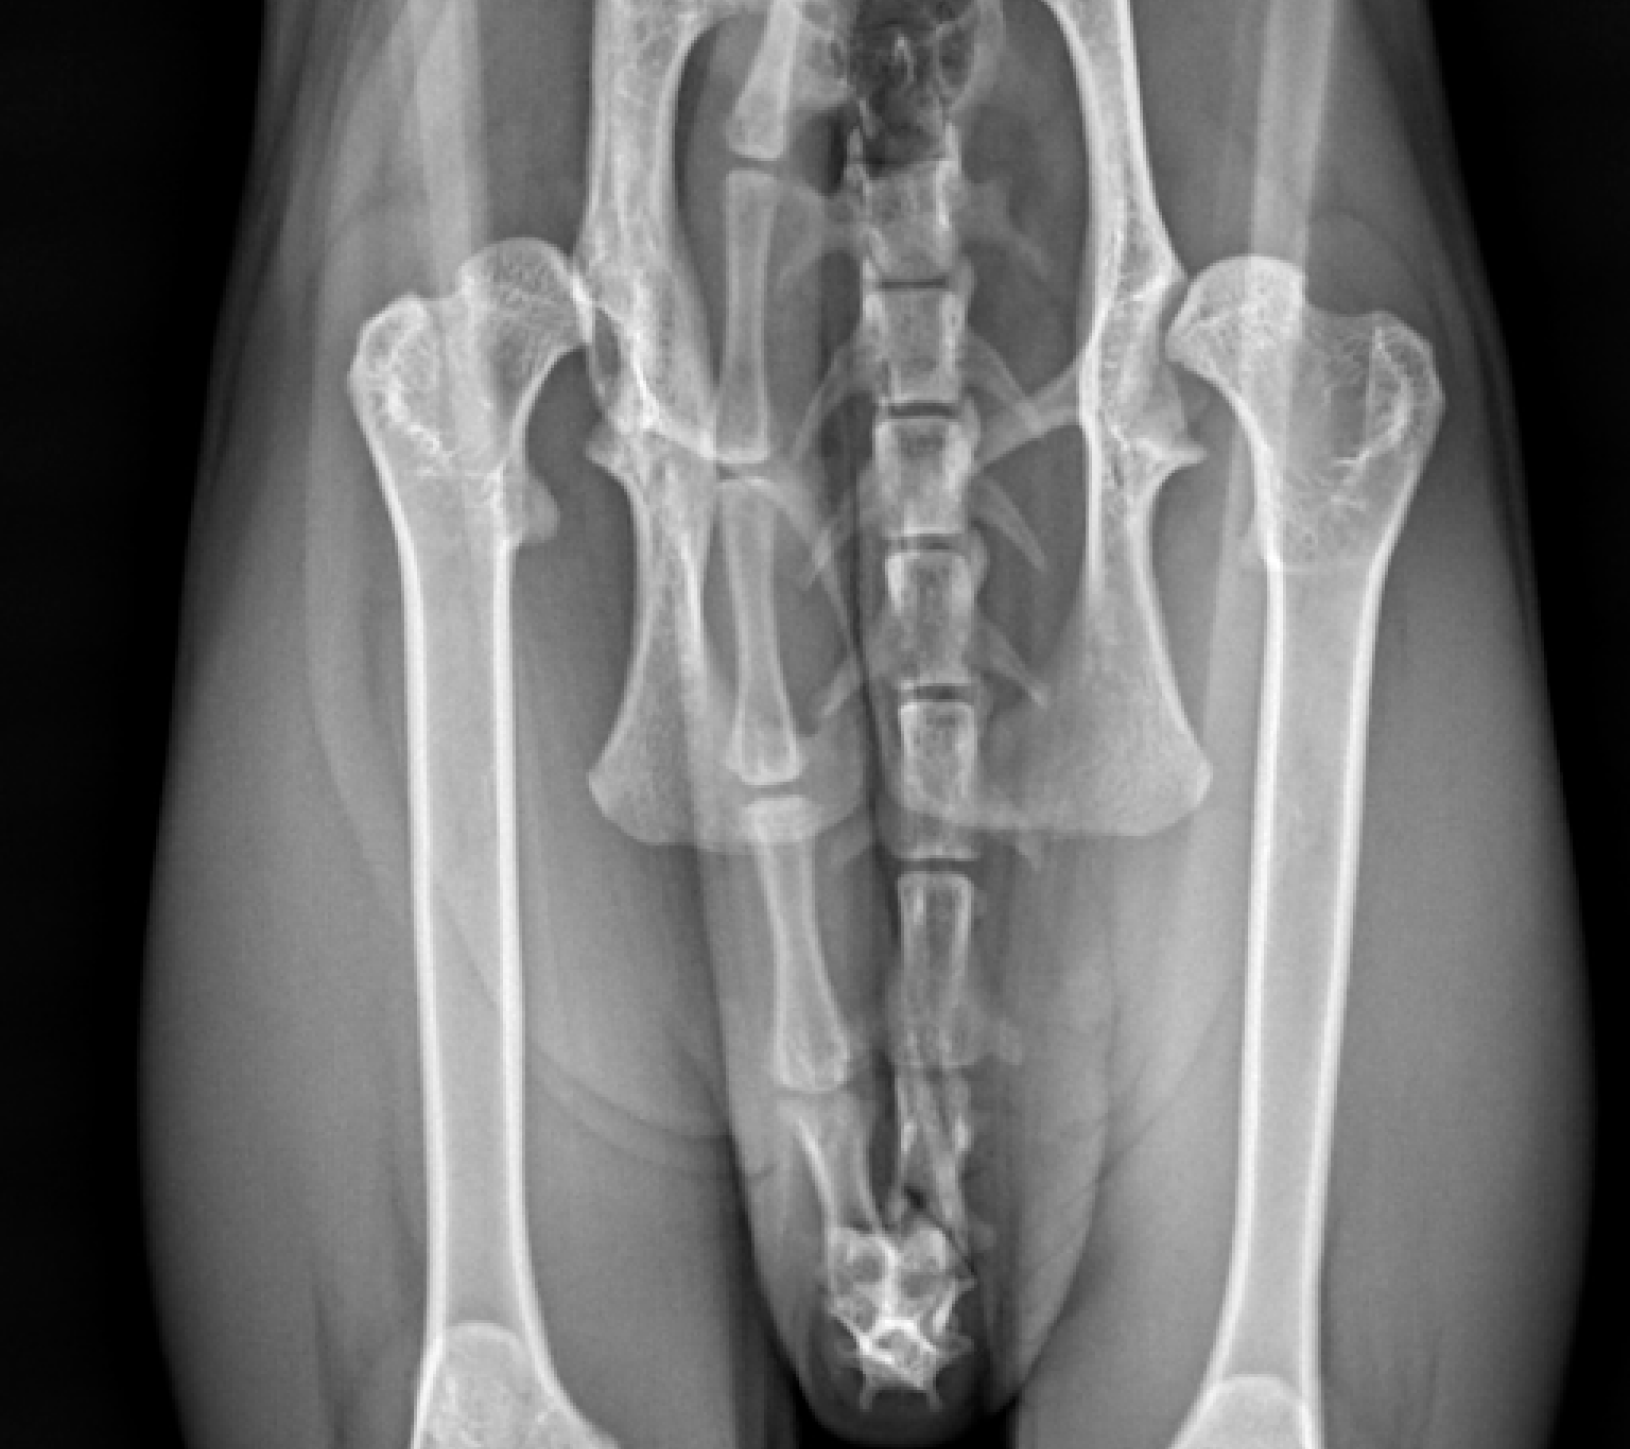

El diagnóstico de la displasia de cadera generalmente se alcanza a través de un completo examen ortopédico y con la realización de un estudio radiológico de las caderas bajo sedación o anestesia general. En este último los hallazgos pueden ser variables, desde incongruencia articular, hasta presencia de signos de degeneración articular (artrosis) como puede ser la deformidad coxofemoral y la aparición de osteofitosis (depósitos anormales de hueso) en la articulación.

- Triple / Doble osteotomía pélvica (TOP / DOP): se trata de un procedimiento que se puede plantear en pacientes en crecimiento de hasta 10 meses de edad aproximadamente dependiendo de la raza o tamaño final estimado del perro. El objetivo de la cirugía es mejorar la congruencia y estabilidad de la articulación coxofemoral. Consiste en la realización de tres o dos cortes (osteotomías) controlados de la pelvis, para estabilizar mediante una placa especial el fragmento acetabular en una nueva posición donde conseguir una mayor cobertura de la cabeza femoral. Es una técnica que solo se puede utilizar en pacientes con laxitud articular pero sin remodelación articular ni signos de osteoartrosis.